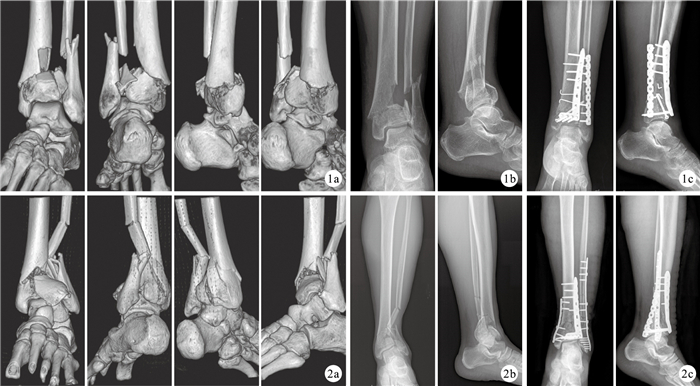

本組手術時間1.8~4.6 h,平均2.4 h;術中出血量200~500 mL,平均310 mL。19例均獲隨訪,隨訪時間12~18個月,平均13.7個月。術后2例踝前正中切口邊緣部分壞死,經短腿石膏托外固定以及換藥后愈合。所有患者6個月恢復正常生活、工作,12~18個月取出內固定物。骨折愈合時間2.5~8.0個月,平均3.6個月。并發創傷性關節炎2例,踝關節不穩定1例,取出內固定物后對癥治療好轉,建議行踝關節融合術。無內固定物松動斷裂、骨不愈合、再骨折、血管神經損傷等并發癥發生。術后12個月,根據Burwell-Charnley影像學評價標準,解剖復位15例,復位一般4例。根據AOFAS踝-后足評分系統評分為62~96分,平均83.79分;獲優11例,良5例,可3例,優良率84.2%。見圖 1、2。